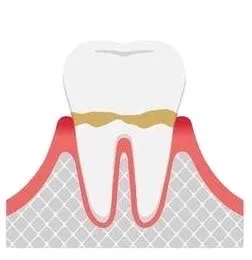

初期歯周病

歯周ポケットが3~4mm程度となり、歯を支える骨が少しずつ溶け始めます。歯肉の腫れや出血に加えて、口臭が気になることもあります。